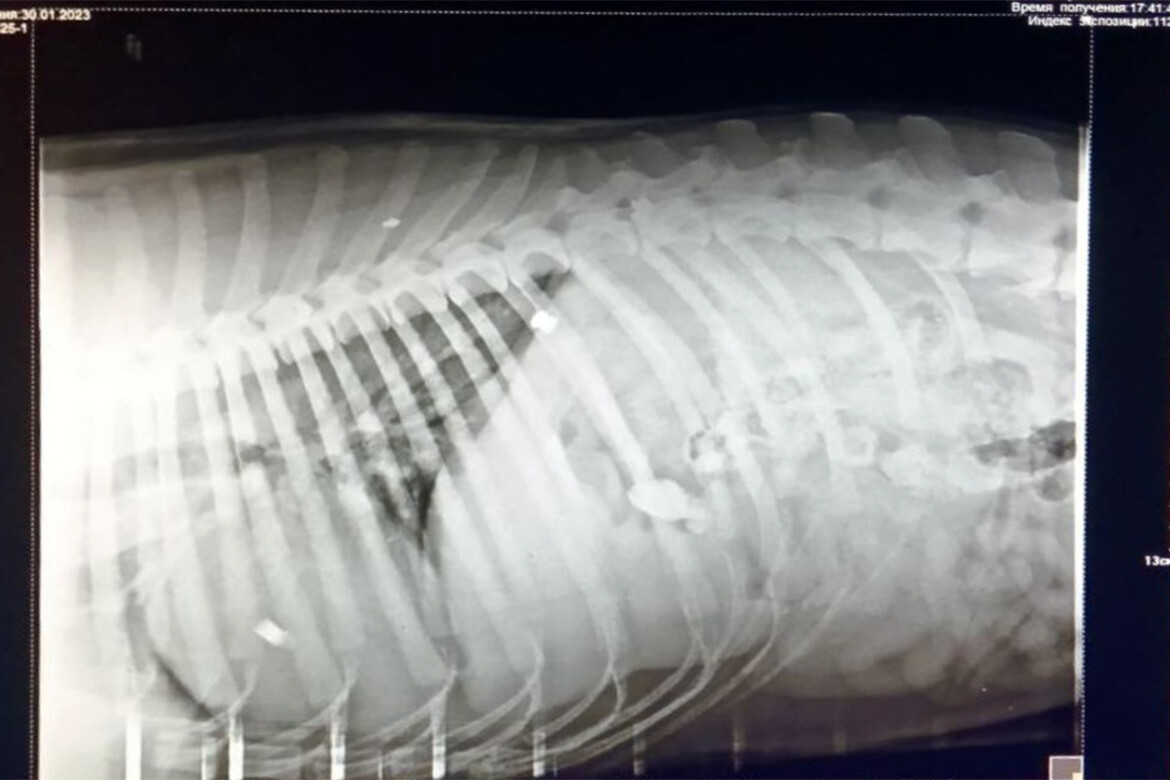

Дворового пса по кличке Дружок, который обычно встречал жителей улицы Рахлина в Казани радостным вилянием хвоста, накануне увидели волочащим за собой задние лапы. Следы крови на черной шерсти заметили не сразу и поначалу предположили, что его сбила машина. Паника и слезы – такой была первая реакция людей на изувеченное животное. Дружка быстро усадили в машину и отвезли в ближайшую ветклинику. Осмотр ветеринара сразу все прояснил – в теле пса нашли дробь. В него выстрелили шесть раз.

Прогноз ветеринара неблагоприятный

«Сегодня пса нужно вести на КТ в другую клинику, на это нужно 17 тысяч рублей. Обследование покажет, сможет ли собака ходить, но ветеринар уже сделал неблагоприятный прогноз – у пса задет спинной мозг. В любом случае понадобится дорогостоящая операция, чтобы спасти его», – рассказывает жительница одного из домов по улице Рахлина Юлия Липатова.